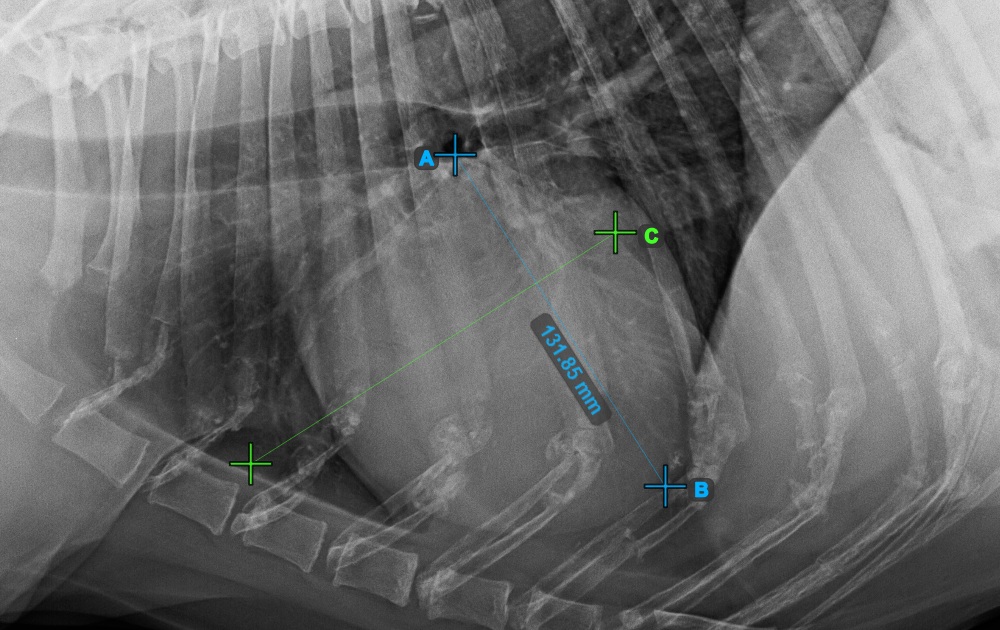

Start the measurement by marking the Bifurcatio tracheae, near the top of the heart.

The image below represents a typical placement of the Bifurcatio tracheae point.